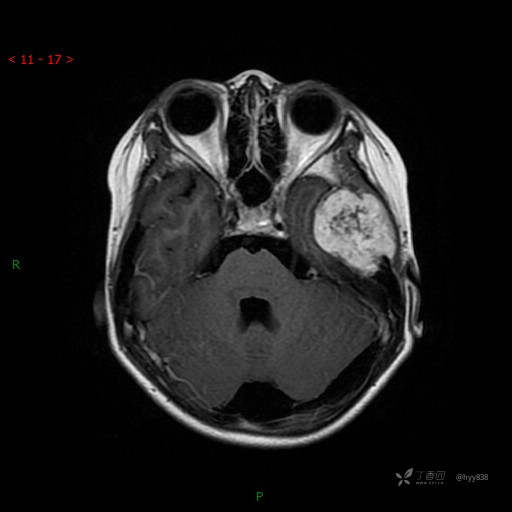

“典藏”病例分享。10岁儿童,头痛头晕一周余,CT、MRI 都有---结果公布~

简要病史:患者于一周前无明显诱因开始出现头痛头晕,无恶心呕吐,无肢体抽搐,无寒颤高热,无腹胀腹泻,无视力下降及视野缺损,上述症状休息后可稍缓解,未引起重视。 2天前患者头痛头晕不适加重,伴有恶心感,无呕吐,遂到当地人民医院行头颅CT检查示:左侧颞部占位性病变,今日家属为求进一步治疗,来我院门诊求治。门诊拟“左侧颞部占位性病变”收入我科。 患病以来,患者精神、饮食、睡眠尚欠佳,大小便如常,体力体重无明显变化。

临床诊断:左侧颞部占位

颅脑CT扫描

MRI增强